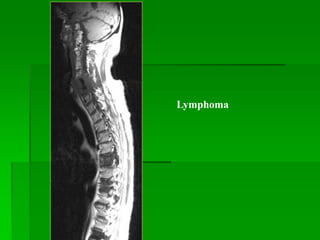

Lymphoma

- Thường gặp ở 40-60 tuổi, nam >nữ.

- MRI: tín hiệu thấp trên T1W, cao không đồng nhất trên T2W,

bắt Gd sau tiêm, có thể gây hủy xương hay chèn ép tủy.

Lymphoma : dày lan tỏa và bắt Gd của chùm đuôi ngựa